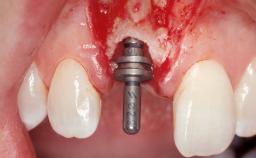

Immediate Flapless Placement of an Implant in a Maxillary Right Lateral Incisor Site

This 43-year-old male patient, a non-smoker, came to our practice because of a fracture of tooth 12 caused by a bicycle accident. Due to the combined para- and infrabony crown and root fracture, tooth extraction, and subsequent implant placement were suggested to the patient as the therapy of choice. The patient had high esthetic expectations with regard to the treatment outcome and asked for an immediate fixed provisional restoration. His individual esthetic risk profile summed up to a medium esthetic risk.